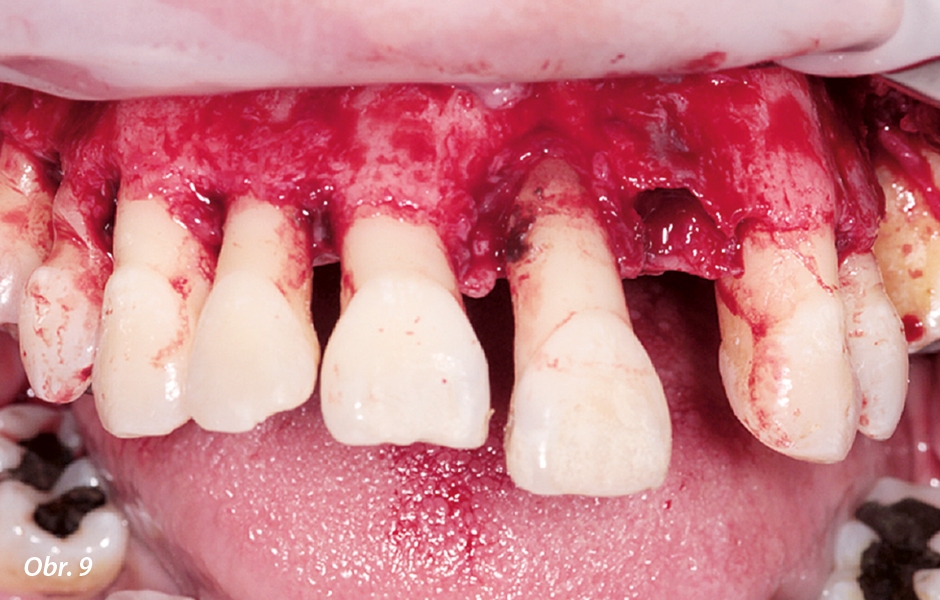

V selhávajícím chrupu horní i dolní čelisti byly přítomny viklavé a posunuté zuby, narušená okluze a ztráta kosti (obr. 3). Aby bylo možno určit nejvhodnější léčebné alternativy s ohledem na kvalitu a denzitu kosti a také přání pacienta, byla analyzována data z CBCT. Při využití pokročilého softwaru (Blue Sky Plan, Blue Sky Bio) mohou být díky všem potřebným pohledům (příčné, koronální, sagitální, axiální) a také díky 3D rekonstruovaným povrchovým modelům detailně vyhodnoceny diagnostické informace pro plánování implantologického zákroku. Lze tak určit vhodné oblasti pro implantáty a pomocí všech dříve zmíněných pohledů následně umístit virtuální implantáty.